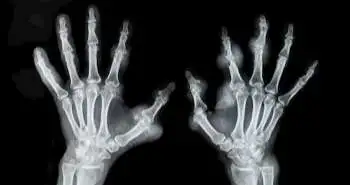

Women with rheumatoid arthritis (RA) and juvenile idiopathic arthritis (JIA) are associated with an increased risk of PTD (preterm delivery). However, the reason behind this is still unclear.

The study recruited; 657 women with RA and 170 with JIA and 564 women without the autoimmune disease (comparison group) who gave birth to live-born infants between the years 2004 to 2017. The JIA and RA group showed an enhanced risk of PTD compared to women without any autoimmune disease. The PTD exhibited a significant relationship with active RA at enrollment and anytime during the pregnancy. The Corticosteroid use during each trimester may be linked to enhanced PTD risk up to two- to five-fold.